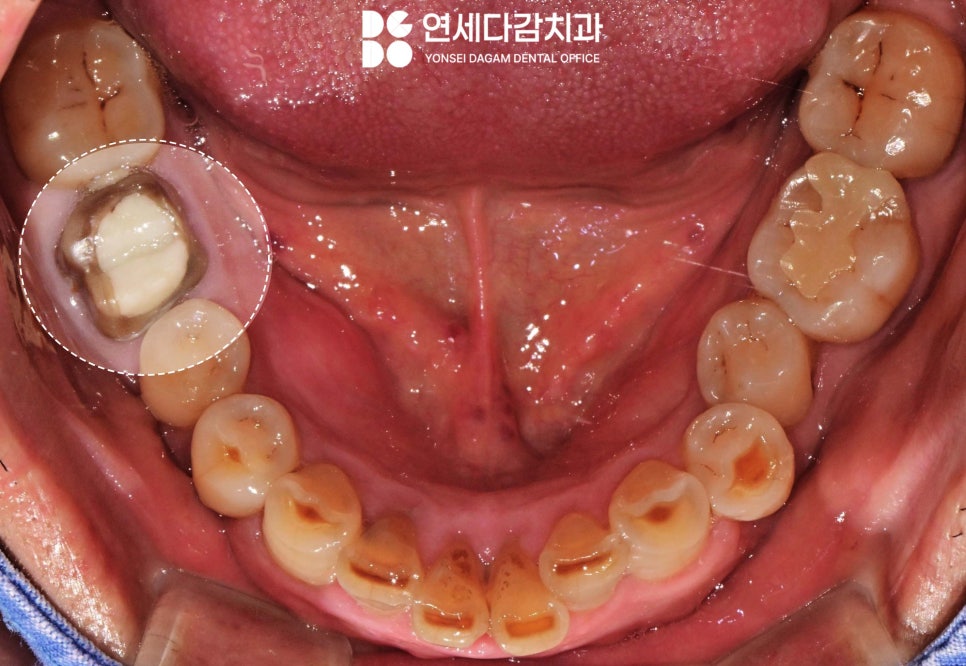

특히 기존에 크라운을 씌운 치아의

보철물이 빠졌을 때

탈락된 채로 방치하면,

음식물이 쉽게 잔류하게 되고

균에 직접적으로 쉽게 감염될 수 있는

환경이 됩니다.

근관치료가 완료된 치아는

신경이 제거된 상태이기 때문에

초기에는 아무런 증상을

느끼지 못하는 경우가 많습니다.

이것이 오히려 문제가 됩니다.

통증이 없어 병소가 진행되는 것을

모르고 지나치게 되기 때문이죠..

이러한 염증이 만성적으로 진행되어

그 범위가 광범위해지면

결국 극심한 통증으로 나타납니다.

이때는 약간의 타진만으로도

참기 어려운 통증을 호소하며,

이 단계에 이르면 그 치아의

보존 가능성은 떨어지게 됩니다.